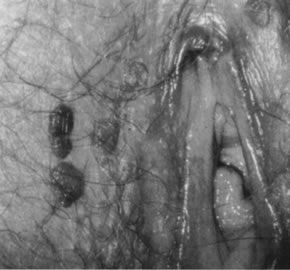

Condylomata acuminata in the vulvar area most commonly involve the perineum, the posterior portion of the vestibule, and the labia minora; less commonly involved are the labia majora, the clitoris, and the mons pubis. Lesions on moist, mucosal surfaces tend to be pink, vascular tumors with finger-like projections (Fig. 15). On keratinized skin, the condylomas are often white or dark because of keratin and pigment formation (Fig. 16). The lesions have a typical histologic appearance of a papillary growth with marked acanthosis, koilocytosis and hyperkeratosis, or parakeratosis. Condylomata acuminata most commonly are associated with HPV-6 and HPV-11.

Fig. 15. Colpophotograph of condylomata acuminata of the vulva. The condylomata near the hymenal ring ( top left )are microconvoluted to a brainlike epithelial arrangement. Condylomata near the outside of the vestibule have an irregular papillary appearance.

Fig. 16. Colpophotograph of condylomata on the inner aspect of the right labium majus. Some lesions are white because of keratin formation.